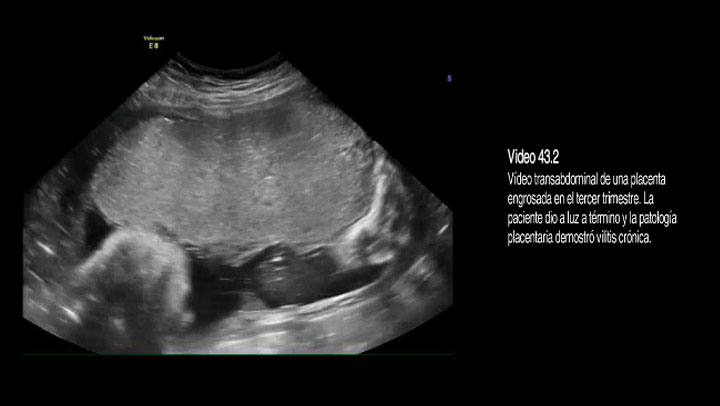

Video 43.02 Placenta gruesa